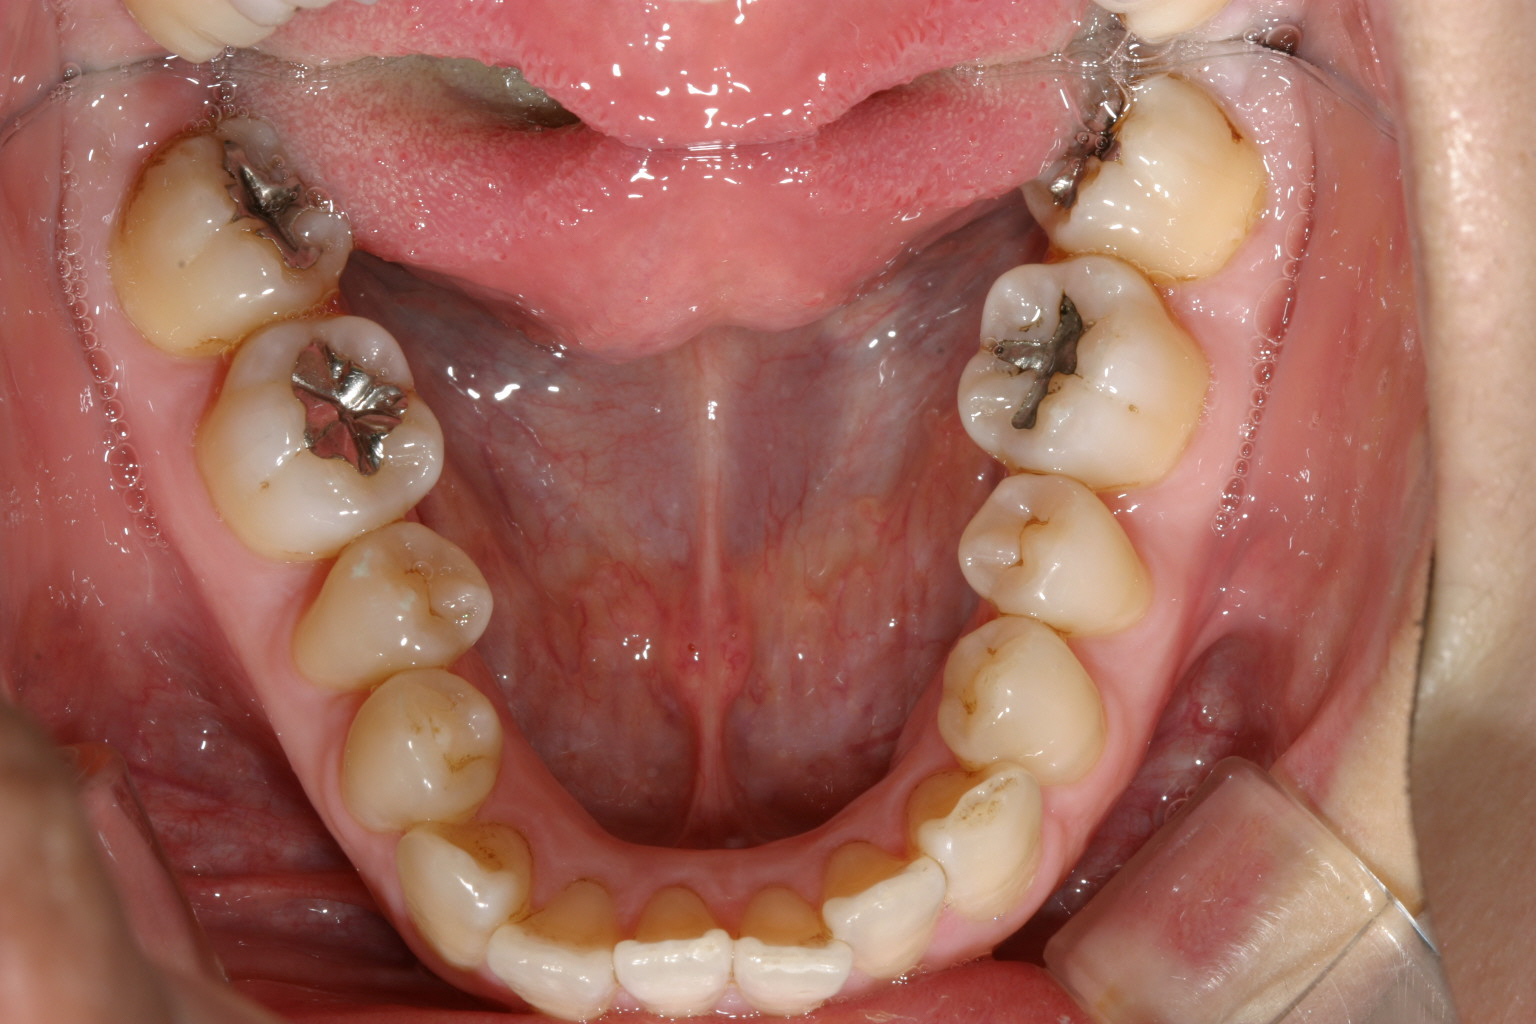

下顎もV字になっています。 又今日臼歯部が左右とも内方に傾斜しています。